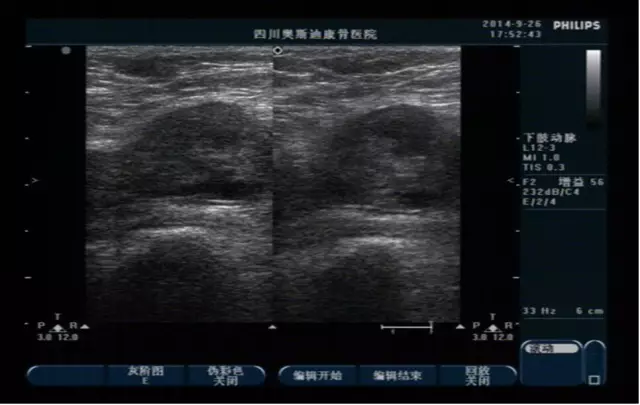

【病案讨论】下肢静脉血栓的诊断和预防保健

今日,四川奥斯迪康骨医院特诊科的医师们在下肢静脉血栓的病案中介绍到,下肢静脉血栓是常见的周围血管疾病,下肢静脉血栓导致的静脉瓣膜功能不全及并发的肺栓塞是病人劳动力及生命安全的一大危险。